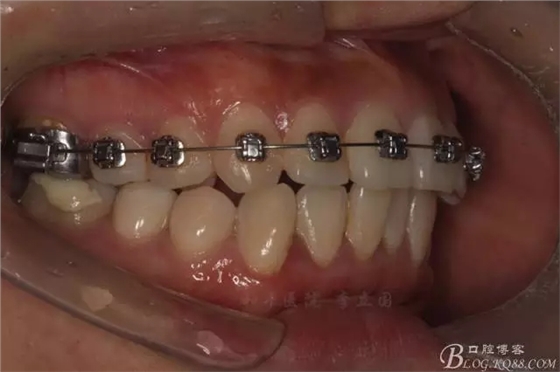

該病例主要為17、27頰側(cè)位同時(shí)伴有伸長(zhǎng),當(dāng)然種植支抗可以解決,但還有簡(jiǎn)單實(shí)用的辦法嗎?如圖,在橫腭桿遠(yuǎn)中延伸出牽引鉤,位置盡量遠(yuǎn)離合平面,7粘舌側(cè)扣,牽引力的方向?yàn)閴旱图吧嘞?,下圖為兩個(gè)月的效果,17已到位,27還未到位。